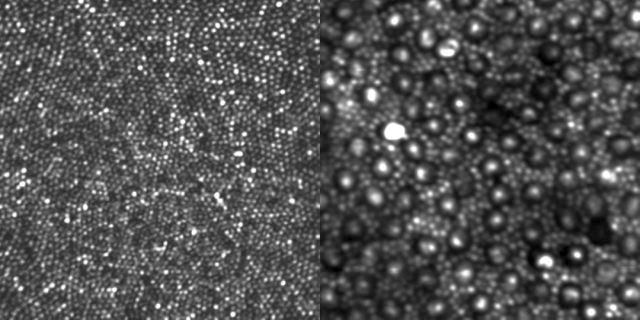

| Adaptive optics has allowed a clearer view of individual retina cells. Left: the fovea region of the retina, showing the cone cells which are involved in forming sharp central vision. Right: a different area of the retina, in which the large bright dots with a dark ring around them are cones, and the more abundant smaller spots are rods. Credit: Alfredo Dubra, Medical College of Wisconsin |